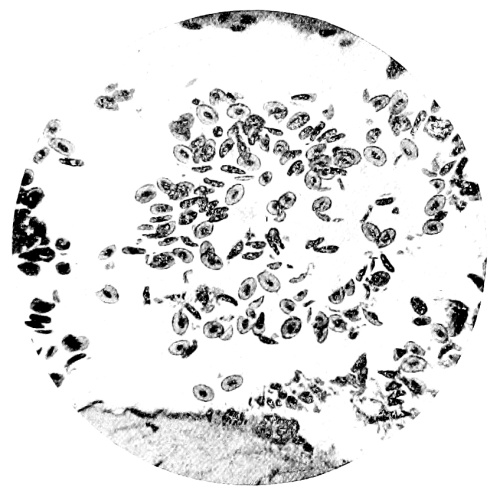

| 10. | Photo-micrograph of Red Blood Corpuscles from Domestic Fowl | 99 |

| 11. | Photo-micrograph of Blood Corpuscles of Fish | 99 |

| 12. | Photo-micrograph of Blood Corpuscles from a Dried Stain of the Blood of a Cod-fish | 100 |

| 13. | Photo-micrograph of a Frog‘s Blood showing oval nucleated Red Corpuscles | 101 |